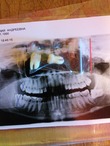

Этот снимок с прошлого раза, горизонтальный еще сидит на месте